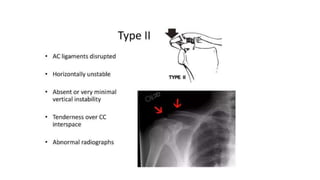

Classification:-